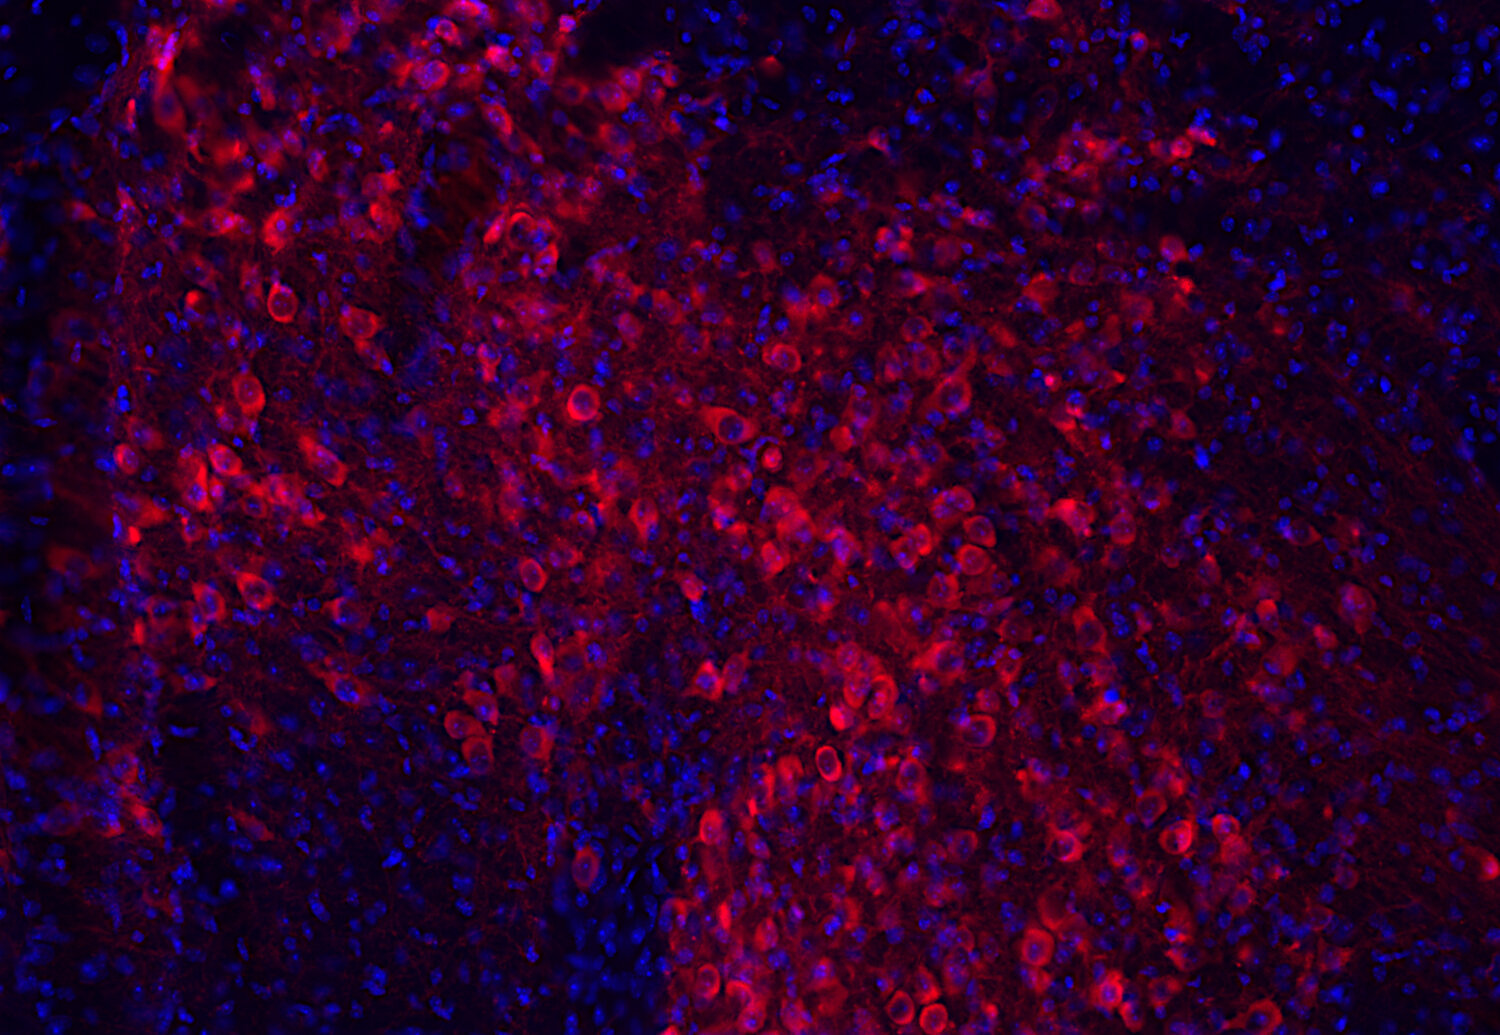

IHC: 1 : 1000 up to 1 : 10000 (see remarks) gallery

Immunohistochemistry (IHC) on 4% PFA perfusion fixed tissue with 24h PFA post fixation. Immunoreactivity is usually revealed by fluorescence or a chromogenic substrate. Some antibodies require special fixation methods or antigen retrieval steps. For details, please refer to the ”Remarks” section.

Cell reports (2023) 423: 112231. 213 211 IHC; tested species: mouse

Tyrosine hydroxylase is one of the key enzymes in the synthesis pathway of catecholamines like adrenalin, noradrenalin and dopamin and is frequently used as a marker for dopaminergic neurons. This neuronal subpopulation is especially affected in Parkinson's disease.